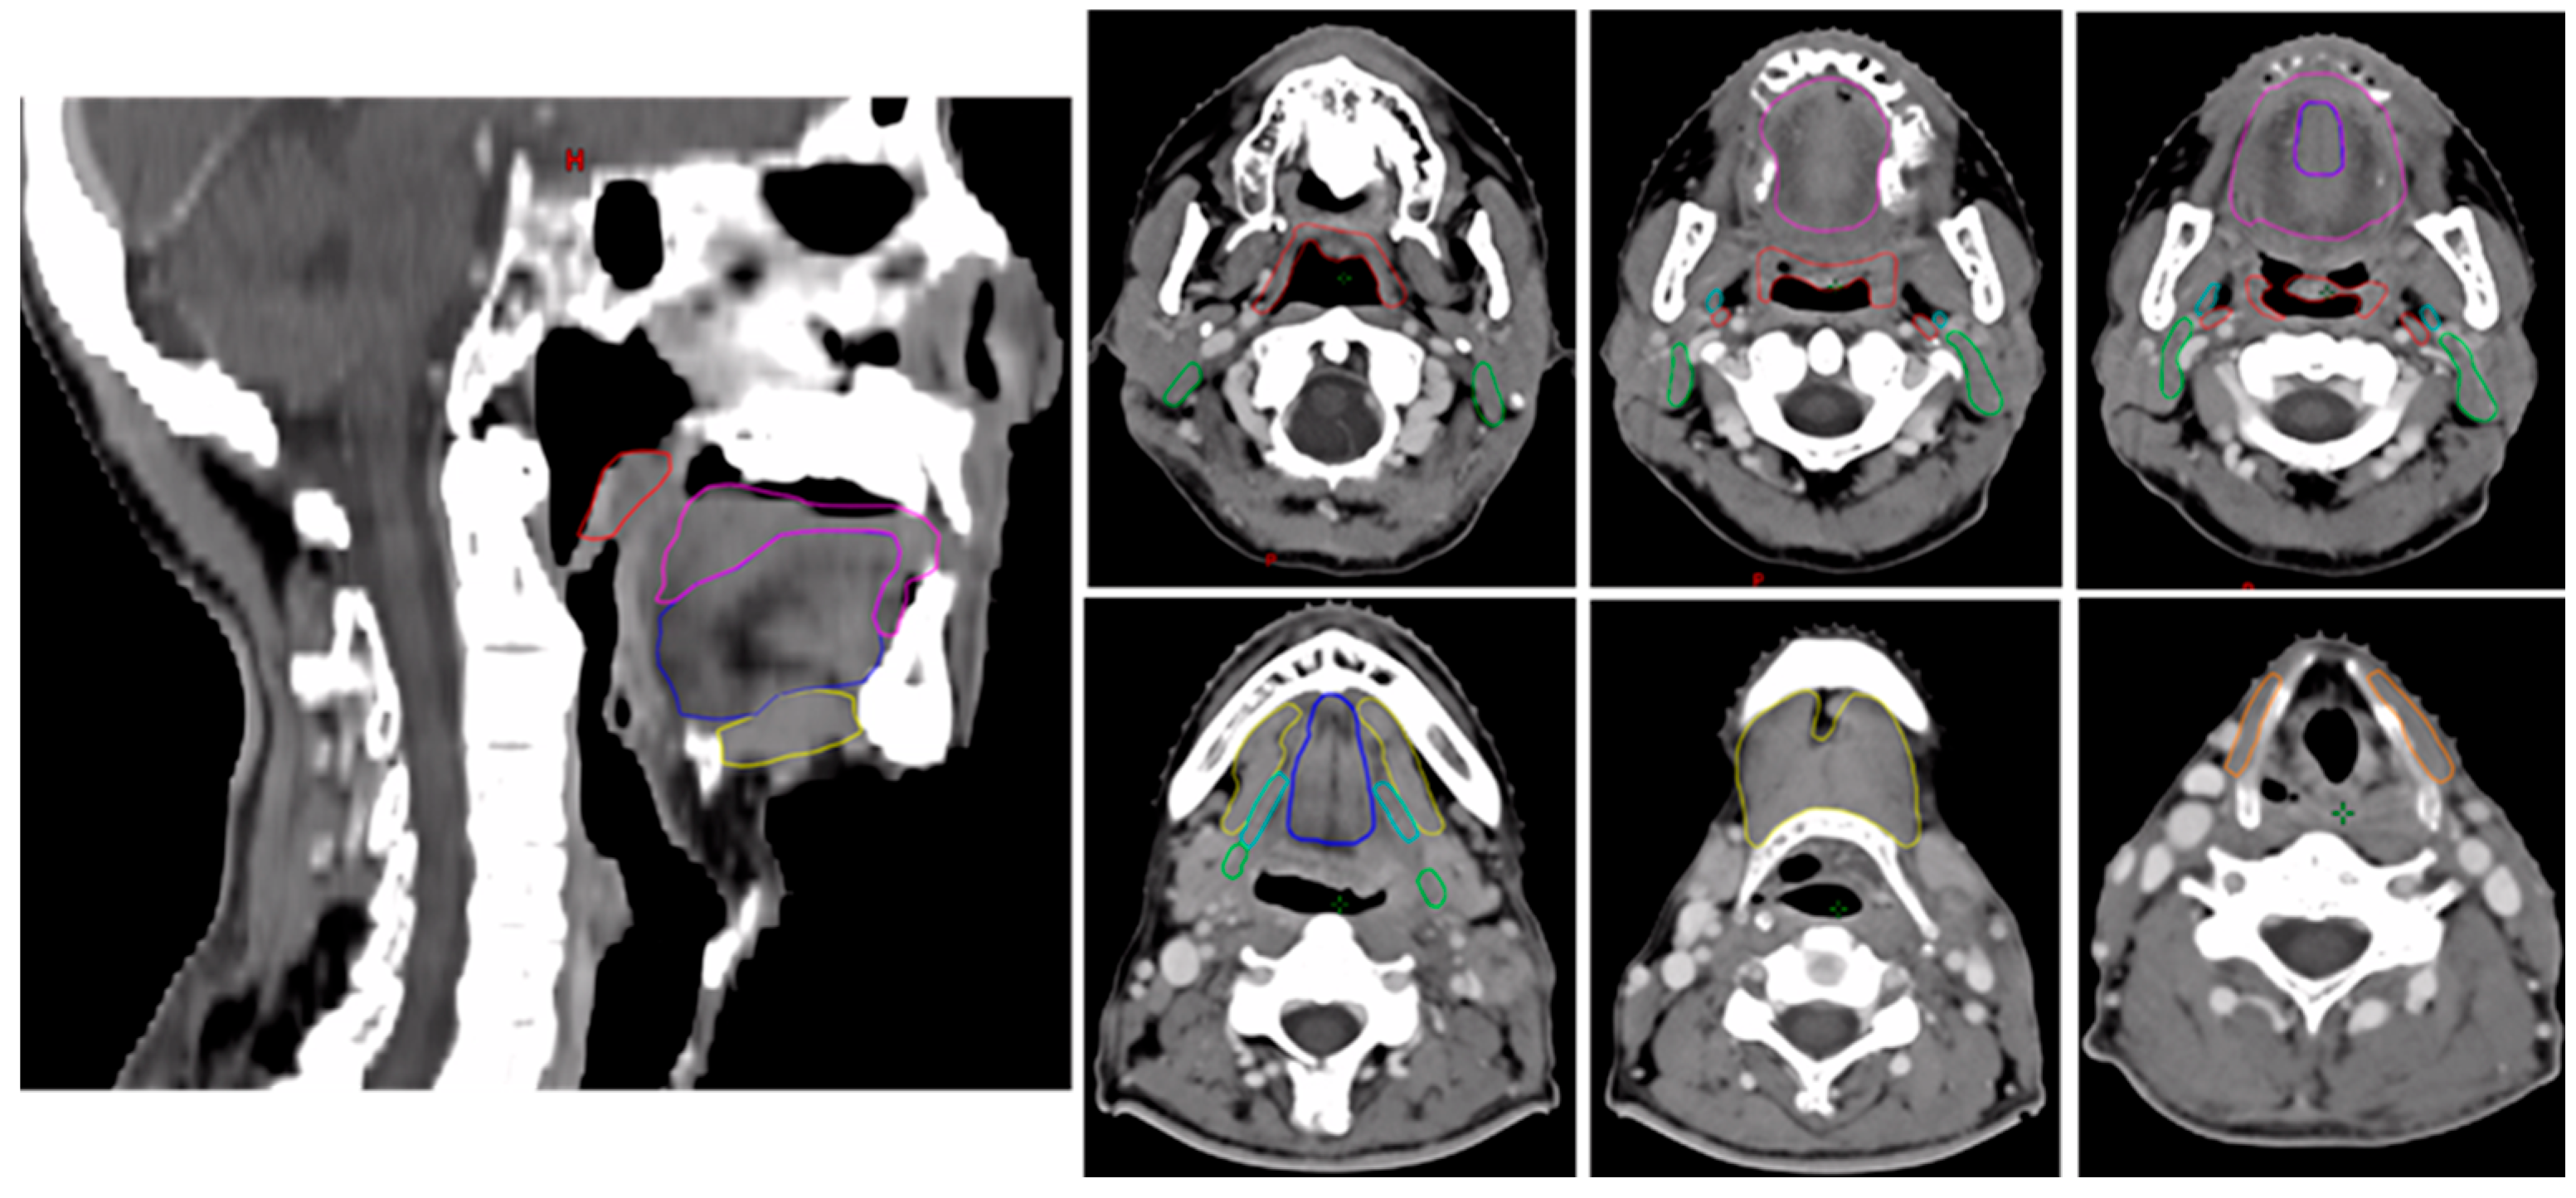

2.2. Radiotherapy Treatment